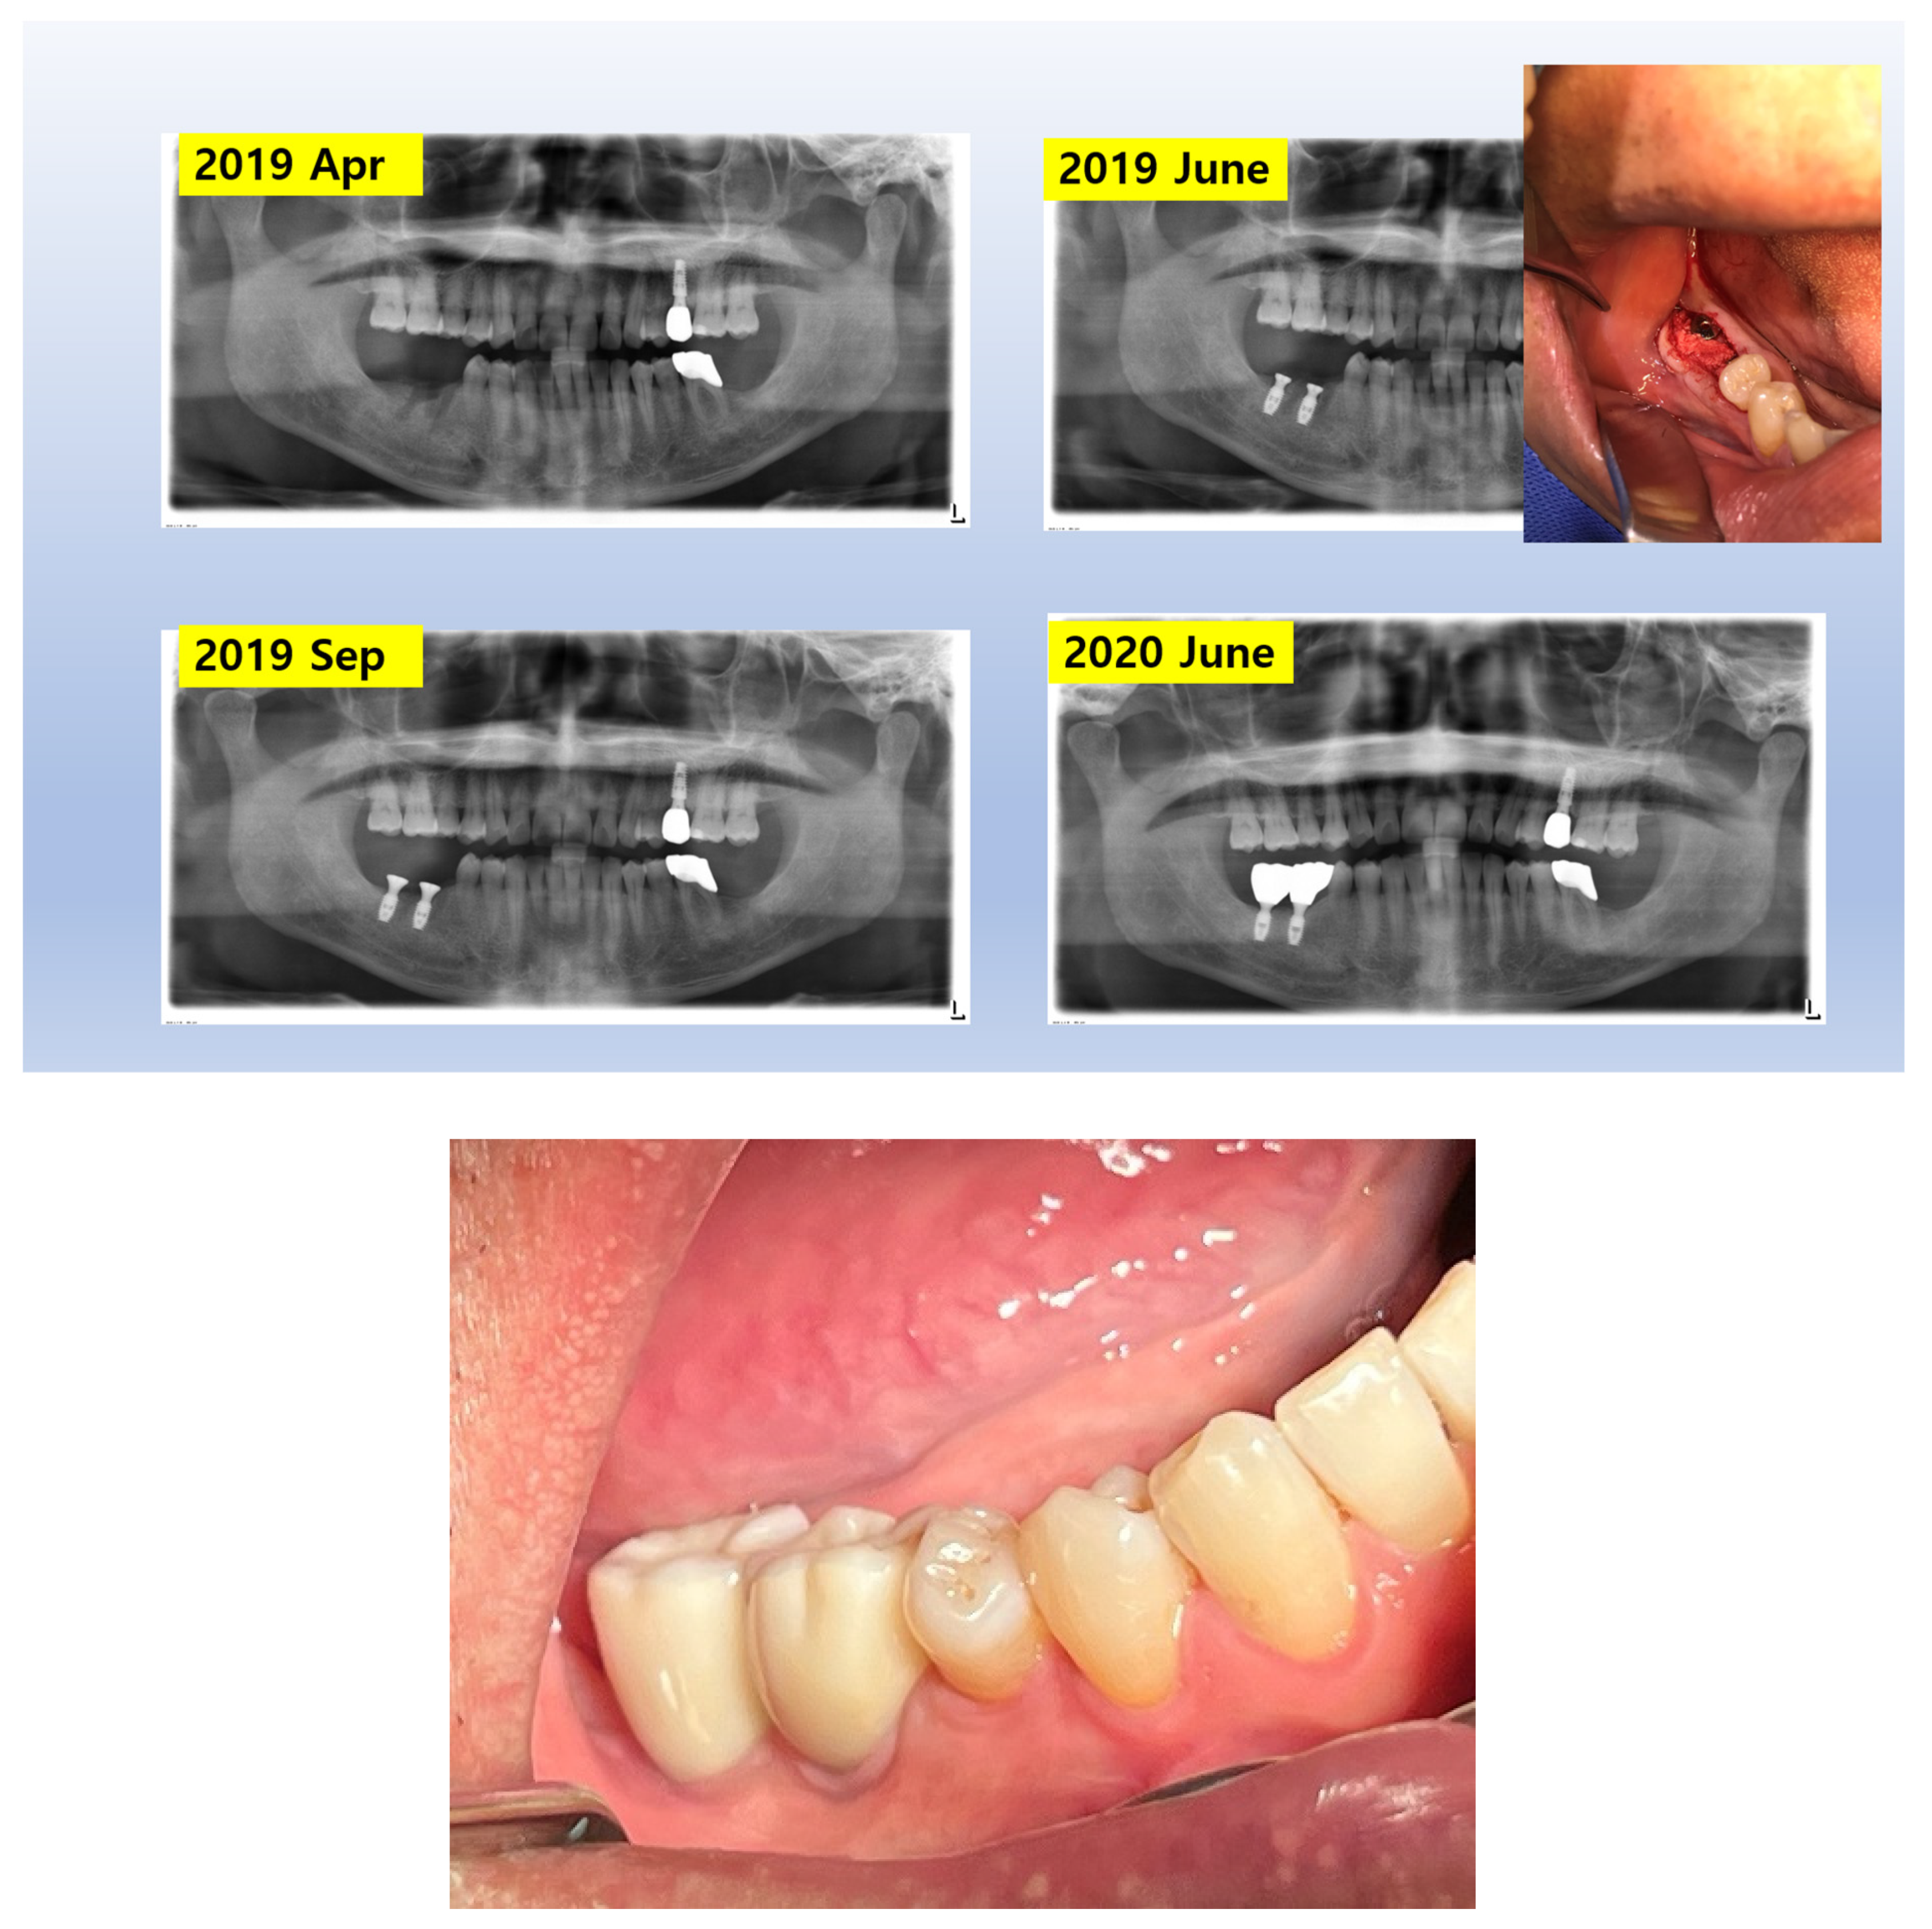

Figure 9. X-Ray Sequence of Healing Abutment Changes. This series of X-rays illustrates the procedural sequences for implant placement and subsequent adjustments. Initially, healing abutments measuring 5 mm in diameter and 2.5 mm in height were placed and covered with primary flap closure. After three months, a second operation was undertaken for the prosthetic procedure. During this stage, the sites were uncovered and longer healing abutments, maintaining the same profile as the initially embedded abutments, were connected to prepare for final prosthesis installation.